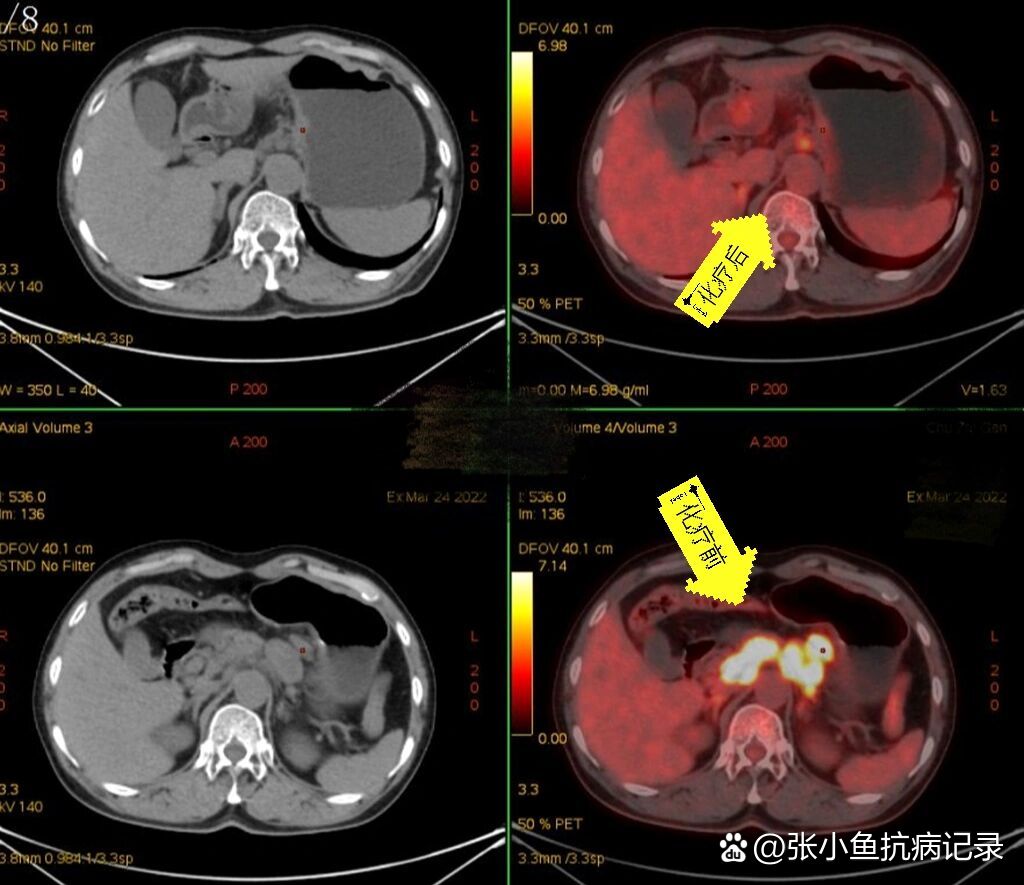

二,确诊胃癌晚期并多发转移

图片尺寸1280x1280